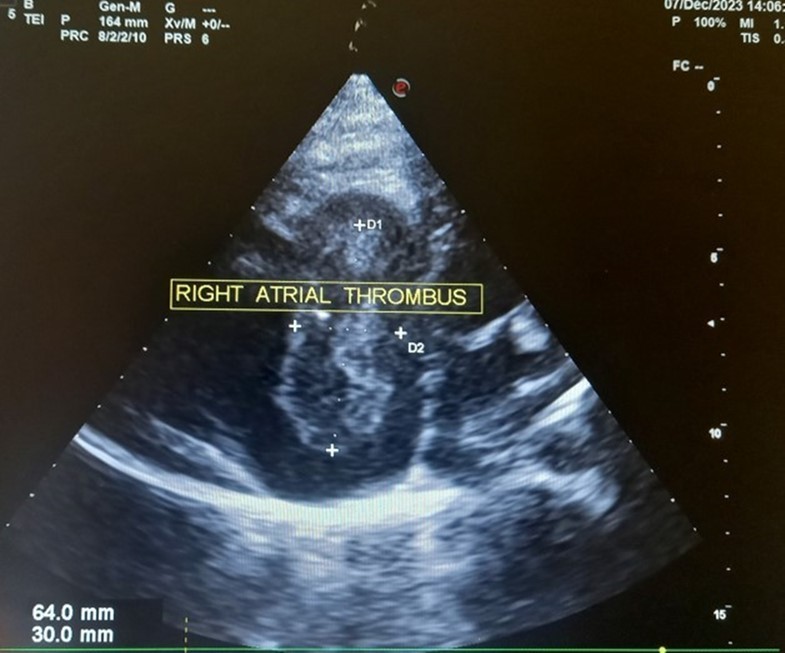

The patient underwent echocardiography (Figure 3 ) showing a low insertion of the septal and posterior leaflets of the tricuspid valve 22 mm below the tricuspid annulus, the anterior leaflet having reduced reduced mobility. Significant dilatation of the the right atrium by atrialisation of the right ventricle (RV). The rudimentary RV and its atrial stump are dilated and responsible for compression of the LV. There was no tricuspid insufficiency. No other associated congenital anomaly. However, we found a large floating thrombus in the right atrium measuring 64 mm x 30 mm in diameter. This was therefore Ebstein's disease at stage C of the Carpentier classification. The apical displacement of the tricuspid septal valve was 22 mm or 15 mm/m2). The surface area of the atrium and the atrialized right ventricle was 45 cm2 , the surface area of the right ventricle and the left cavities was 30 cm2 , the Celermajer index was calculated at 1.4 ( Grade 3).

Figure 3.Transthoracic echocardiography, apical four chambers view . Apical displacement of the tricuspid valve (a) and right atrial thrombus (b).

In our case, the patient had, type C of EA and Grade 2. The investigation also revealed a large thrombus floating in the right atrium and no obvious regurgitation of the tricuspid valve. In addition, the septa was intact, there was no persistence of the ductus arteriosus, the pulmonary and aortic pathway were unobstructed.

Our case highlights a rare form of Ebstein's disease with a large right intra-atrial thombus. It is a rare disease discovered late in adulthood with no vicarious shunt. Echocardiography is used to establish the diagnosis and to assess its severity. Ebstein's anomaly is tricuspid valve and right ventricular malformation with variability in anatomy, pathophysiology, and clinical presentation which cannot be managed surgically in our resource-limited setting. The great anatomical heterogeneity of EA generates a wide spectrum of clinical features at presentation which cannot be managed surgically in our context of limited resources. Hence the importance of antenatal ultrasound diagnosis with a view to possible termination of pregnancy.